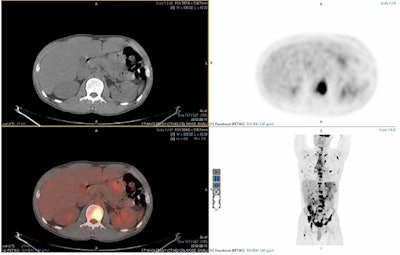

F-18 FDG-PET/CT is widely used for staging of high-grade lymphoma. Evaluation of scans can be time-consuming, depending on complexity and disease extent, taking up to an hour to analyze and report, Scarsbrook said.

Nine readers (three trainees, three junior, and three senior consultant radiologists) from three imaging centers participated, with 15 real-world clinical lymphoma staging PET/CT images evaluated twice -- initially, using a standard PET/CT reporting workflow and again after a six-week gap using the AI-assisted workflow.